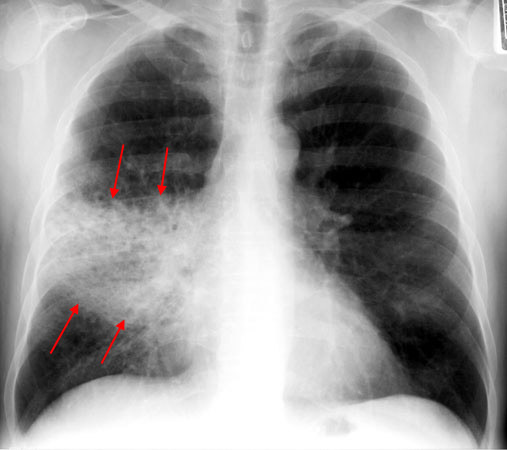

What might a CXR show for pneumonia?